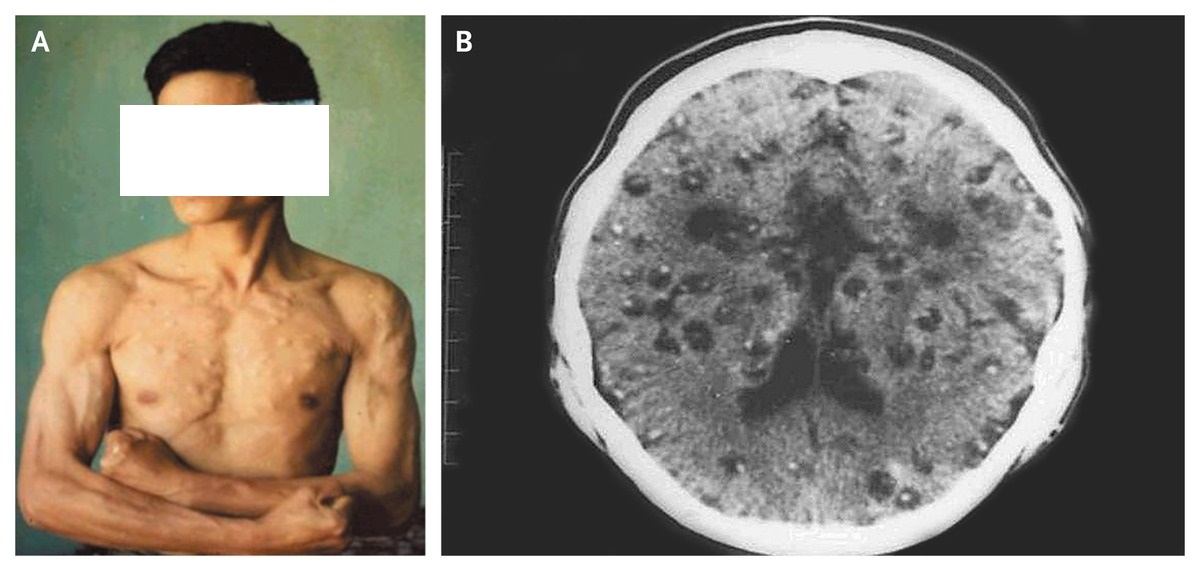

A 42-year-old man presented with seizures and approximately 300 palpable intramuscular cysts, with 54 cysts on his head, face, and neck, 110 on his chest and back, 86 on his arms, and 52 on his legs (Panel A).

During the 3 years preceding presentation, he reported having a chronic headache and witnessing the development of intramuscular cystic nodules on his arms and his upper body.